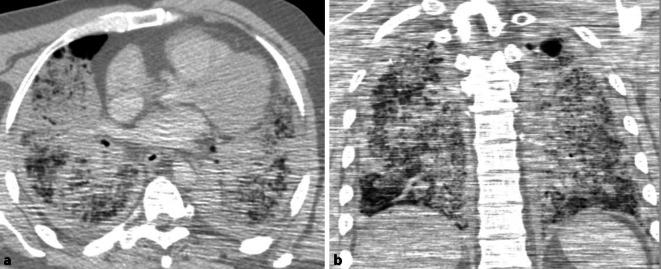

Forensic medicine and pathology involve specific health risks, whereby health workers are dealing with microorganisms, cells or parasites, which are referred to as biological agents. Biological agents are divided into four categories according to § 3 of the Biological Agents Ordinance. The newly identified coronavirus, severe acute respiratory syndrome, coronavirus 2 (SARS-CoV-2) that has spread rapidly around the world is placed into category 3 of the Biological Agents Ordinance, meaning pathogens that can cause serious illnesses in humans and may pose a risk to workers. The Robert Koch Institute, the German government's central scientific institution in the field of biomedicine issued the announcement, that aerosol-producing measures (including autopsies) of SARS-CoV‑2 infected bodies should be avoided, despite the fact that autopsies are an important source of understanding the pathomorphological course of new diseases. The first German case of death due to a proven SARS-CoV‑2 infection is presented with global multifocal reticular consolidation in the post-mortem computed tomography (CT) scan, a macroscopic and microscopic viral pneumonia and viral RNA of SARS-CoV‑2 in pharyngeal mucosa and lung tissue.

法医学和病理学涉及特定的健康风险,卫生工作者会接触微生物、细胞或寄生虫,这些被称为生物制剂。根据《生物制剂条例》第3条,生物制剂分为四类。新发现的在全球迅速传播的冠状病毒,即严重急性呼吸综合征冠状病毒2(SARS-CoV-2),被列入《生物制剂条例》第3类,意味着这些病原体可导致人类严重疾病,并可能对工作人员构成风险。德国政府生物医学领域的中央科学机构罗伯特·科赫研究所发布公告称,尽管尸检是了解新疾病病理形态学过程的重要来源,但应避免对感染SARS-CoV-2的尸体采取产生气溶胶的措施(包括尸检)。德国首例经证实因SARS-CoV-2感染死亡的病例,尸检计算机断层扫描(CT)显示为全球多灶性网状实变,有宏观和微观的病毒性肺炎,以及咽黏膜和肺组织中的SARS-CoV-2病毒RNA。